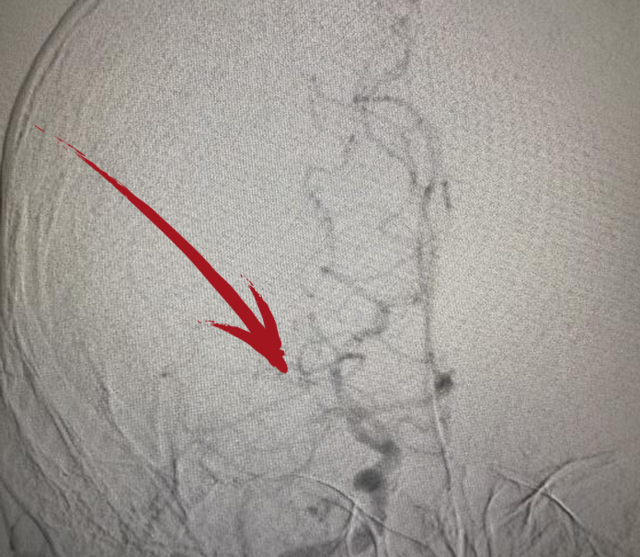

▲术后DSA提示右侧大脑中动脉已开通